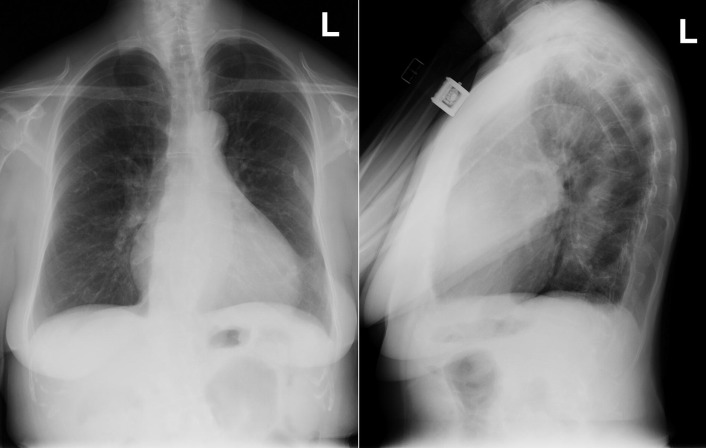

Enlargement of the left atrium is present in the majority of cases of hypertrophic cardiomyopathy ( Figs 14-1 to 14-4 ). Left atrial enlargement is greater in patients with hypertrophic cardiomyopathy when there is concurrent mitral insufficiency. The degree of left ventricular enlargement is variable but is usually mild and consistent with left ventricular hypertrophy. About 50% of cases have cardiomegaly, usually mild to moderate. Mitral annular calcification is common.